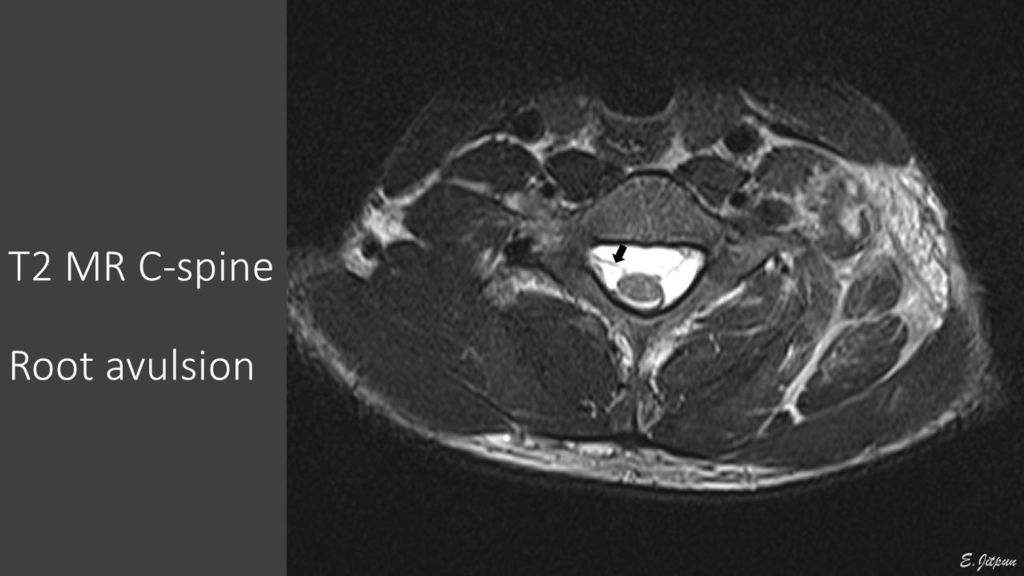

- การตรวจทางรังสีวิทยา ได้แก่ การทำ MRI ของกระดูกและไขสันหลังส่วนคอ เพื่อตรวจว่ามีภาวะไขสันหลังบาดเจ็บร่วมด้วยหรือไม่, มีการฉีกขาดของเส้นประสาท (avulsion) ตั้งแต่ระดับไขสันหลังหรือไม่ และการทำ MRI brachial plexus เพื่อวินิจฉัยการบาดเจ็บของเส้นประสาทในส่วนที่อยู่ถัดออกไปจากกระดูกคอ

- ในผู้ป่วยบางรายพบมีเส้นประสาทขาดออกจากไขสันหลัง (avulsion injury) ในผู้ป่วยกลุ่มดังกล่าว มักเกิดจากการบาดเจ็บที่รุนแรง และมักจะไม่หายเอง จึงมักทำการผ่าตัดค่อนข้างเร็วในผู้ป่วยกลุ่มนี้ โดยทั่วไปมักผ่าตัดในระยะเวลา 2-6 เดือน